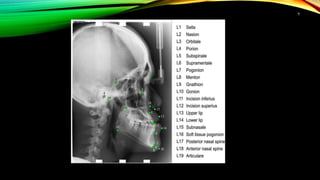

CEPHALOMETRIC LANDMARKS

repr Represents actual anatomic landmarks of the skull

obtained secondarily from anatomic landmarks

UNILATERAL LANDMARKS

• NASION (Na) – most anterior point on frontonasal suture

10

• MENTON(Me) – lowest point on the symphyseal outline of the chin.

• BASION(Ba)- most inferior point in the sagittal plane on the anterior rim of the

BILATERAL LANDMARKS

• ORBITALE(Or)- lowest point on inferior rim of orbit.